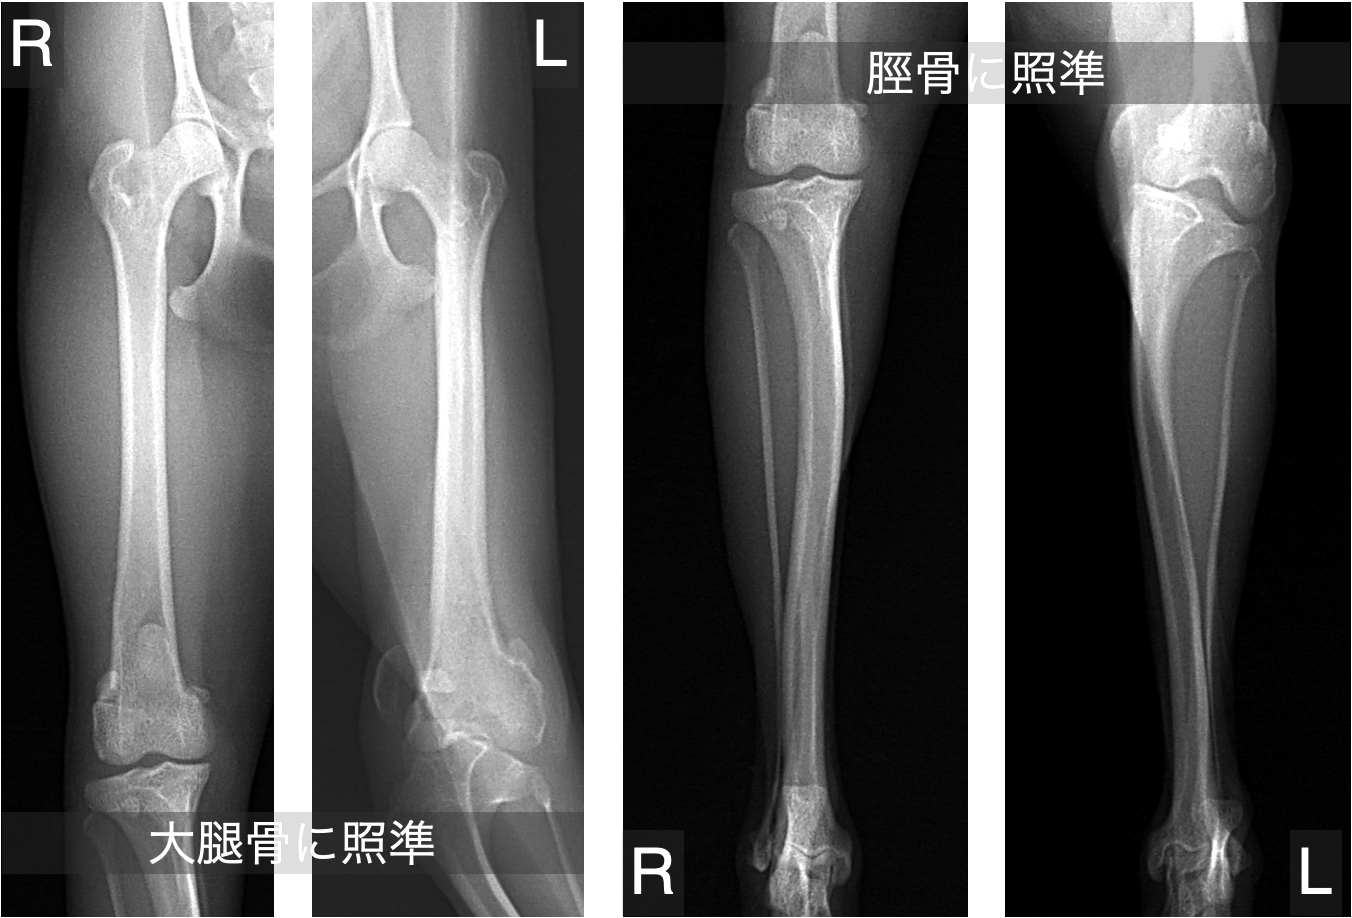

レントゲン検査で骨の変形が疑われる場合には、より詳しい評価のためにCT検査をおすすめしています。

レントゲンでは全体像はつかめても、骨の捩れや傾きといった詳細な情報までは正確に把握できないことがあるからです。

以下は、グレード4の膝蓋骨脱臼でよくみられる骨の変形の一例です。

ただし、骨の変形は症例ごとにその部位や程度が異なるため、CTによる三次元的な形態解析を行うことが、適切な手術計画を立てるうえで重要です。

骨の変形が疑われる場合には、以下のような段階を踏んで安全かつ精度の高い手術を行います。